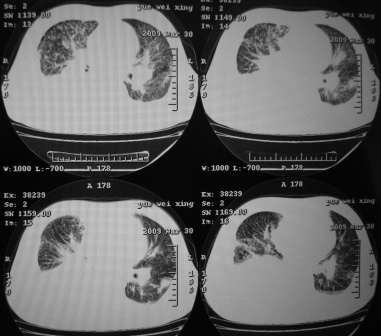

xx 男 43岁

右肺下叶支气管中断闭塞,右下肺见不规块影,并胸腔积液,考虑肺中央型肺癌继发下叶不张,\\双侧胸腔积液,心包积液。

右侧中央型肺癌伴右肺下叶不张,双肺及纵隔淋巴转移,双侧胸腔积液,心包积液。

1)考虑右侧中央型肺癌伴右肺下叶不张,双肺及纵隔淋巴转移。2)双侧胸腔积液,以右侧为甚。3)心包积液。

1.两肺继发型tb。

2.右侧中央型肺癌并双肺及纵隔淋巴转移,心包积液,双侧胸腔积液伴右肺下叶肺不张。

考虑右肺下叶中心性肺癌并纵隔淋巴结、双肺转移伴右肺下叶阻塞性肺不张;双侧胸水,右侧为著;心包积液